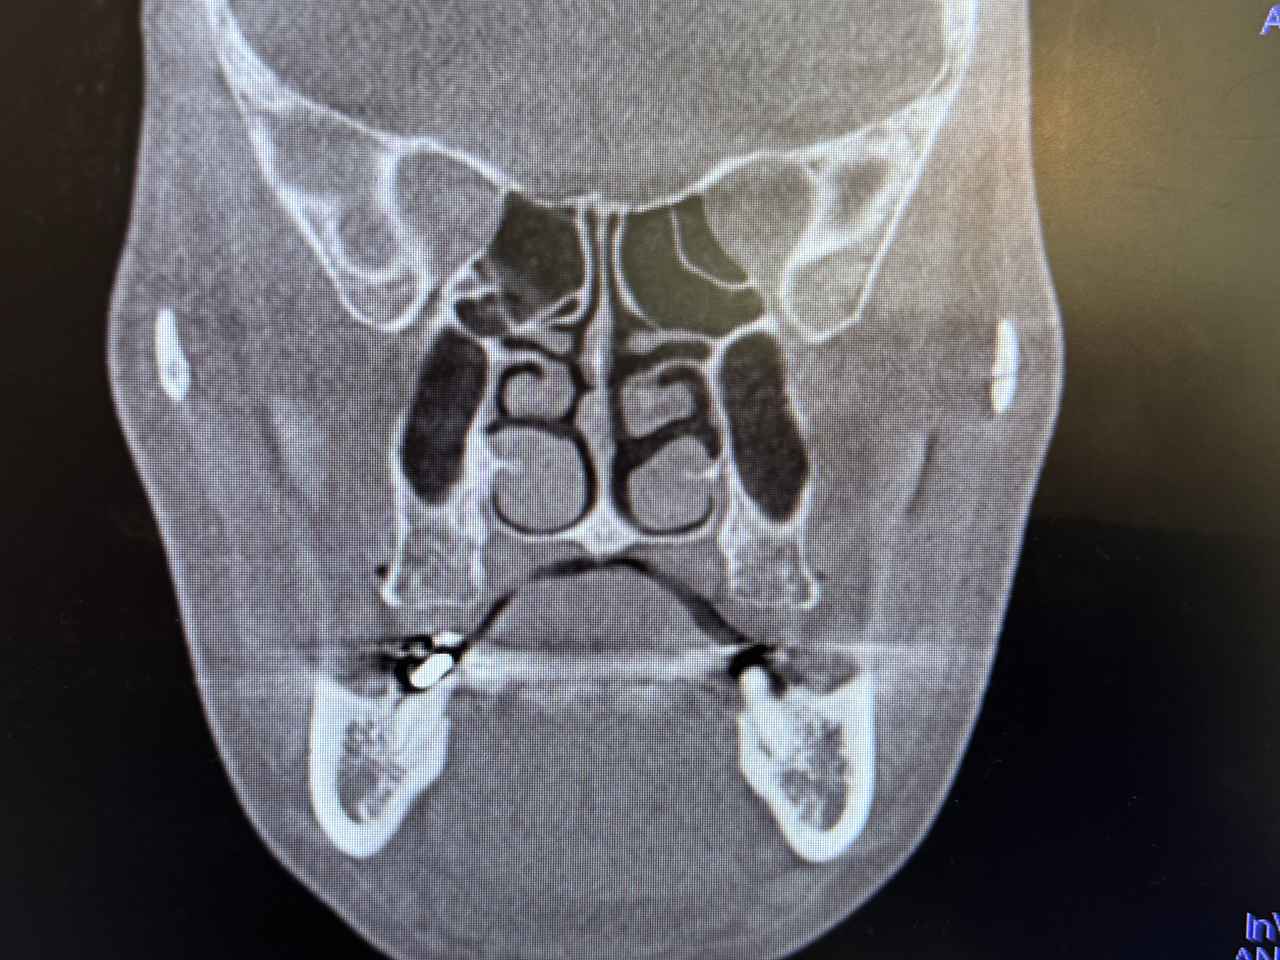

鼻の周りが詰まっているとのこと。鼻づまりなんて体験なかったのでショックでした。

歯科用CTは、顎の骨や歯の位置を立体的に捉えることができるため、従来のレントゲンでは見えにくかった細部まで確認することができます。特に「こどもと女性の歯科クリニック」では、かみ合わせの診断に加えて、今回は、以下のような項目もチェックしてくれました。

頭位や頸椎の傾き:

姿勢のクセや左右差が、顎の位置やかみ合わせに影響していることがあります。

骨格のバランス:

顔の左右差や骨の成長具合など、全身の姿勢にも関係する情報が得られます。

姿勢と口腔の関係は、想像以上に深い

姿勢が悪いと、顎が後方に下がり、かみ合わせがズレたり、気道が狭くなったりすることがあります。その結果、口呼吸になりやすくなったり、歯並びに影響が出たりすることも。歯科用CTは、こうした“見えない原因”を可視化することで、より根本的な治療や予防につなげることができます。歯のことだけでなく、姿勢や呼吸まで見てもらえるなんて驚きでした。